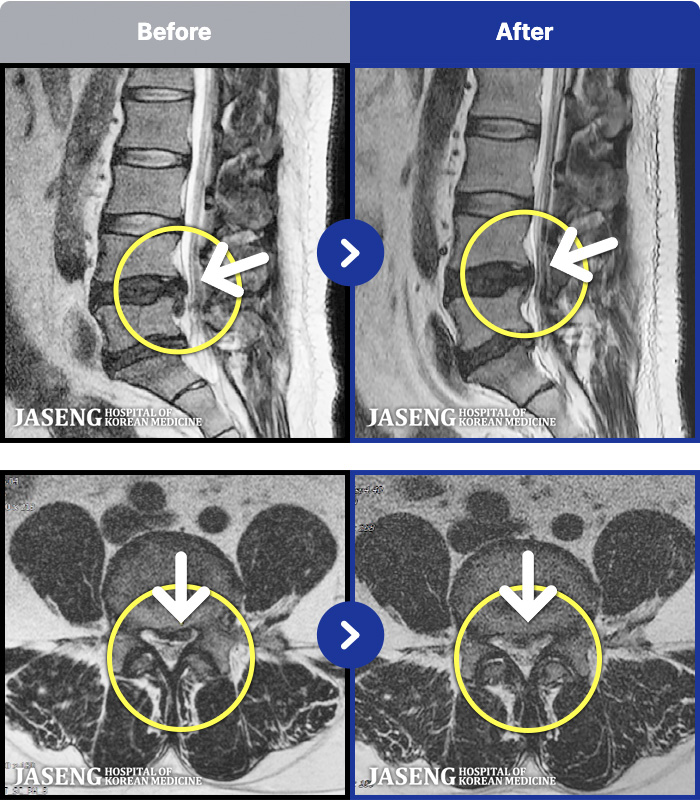

62 MRI ũ ʸ Ȯϼ.